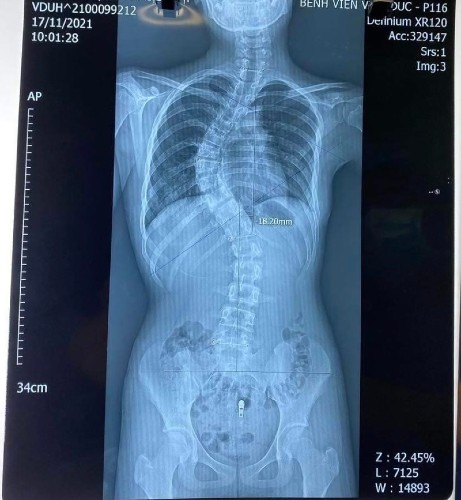

Phẫu thuật chỉnh vẹo cột sống có thể được thực hiện bằng phương pháp mở hoặc phẫu thuật nội soi. Trong quá trình phẫu thuật, các bác sĩ sẽ sử dụng các dụng cụ y tế để nắn chỉnh vị trí của cột sống và gắn các vít nhỏ vào cột sống để giữ vị trí mới.